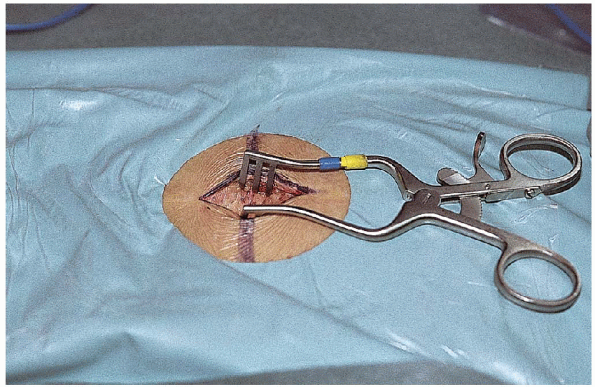

microretractor, a collection of small Kerrisons, pituitaries, and

curettes, although surgeons often have other personal preferences for

instruments to use through the small incision (Fig. 17-8). Small

microretractors have a tendency to tilt, lateral side up, in small

wounds. To correct this tendency, one can hook a chain with a weight

over the lateral blade of the retractor system and hang it off the edge

of the table. A good resource for a hook, chain, and weight is a hip

self-retractor system (see the section on surgical procedure for

further detail).